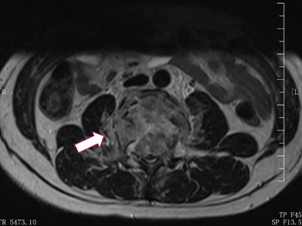

骨科张海龙主任对小郑进行了全面的体格检查,评估了脊柱四肢的运动、感觉和神经反射等情况,并加做了腰椎核磁共振检查。根据影像检查和其他检查结果,发现小郑是腰3椎体爆裂性骨折的骨折碎块压迫脊髓,引起双下肢的不完全性瘫痪,并且合并有马尾神经损伤。

腰椎MRI显示